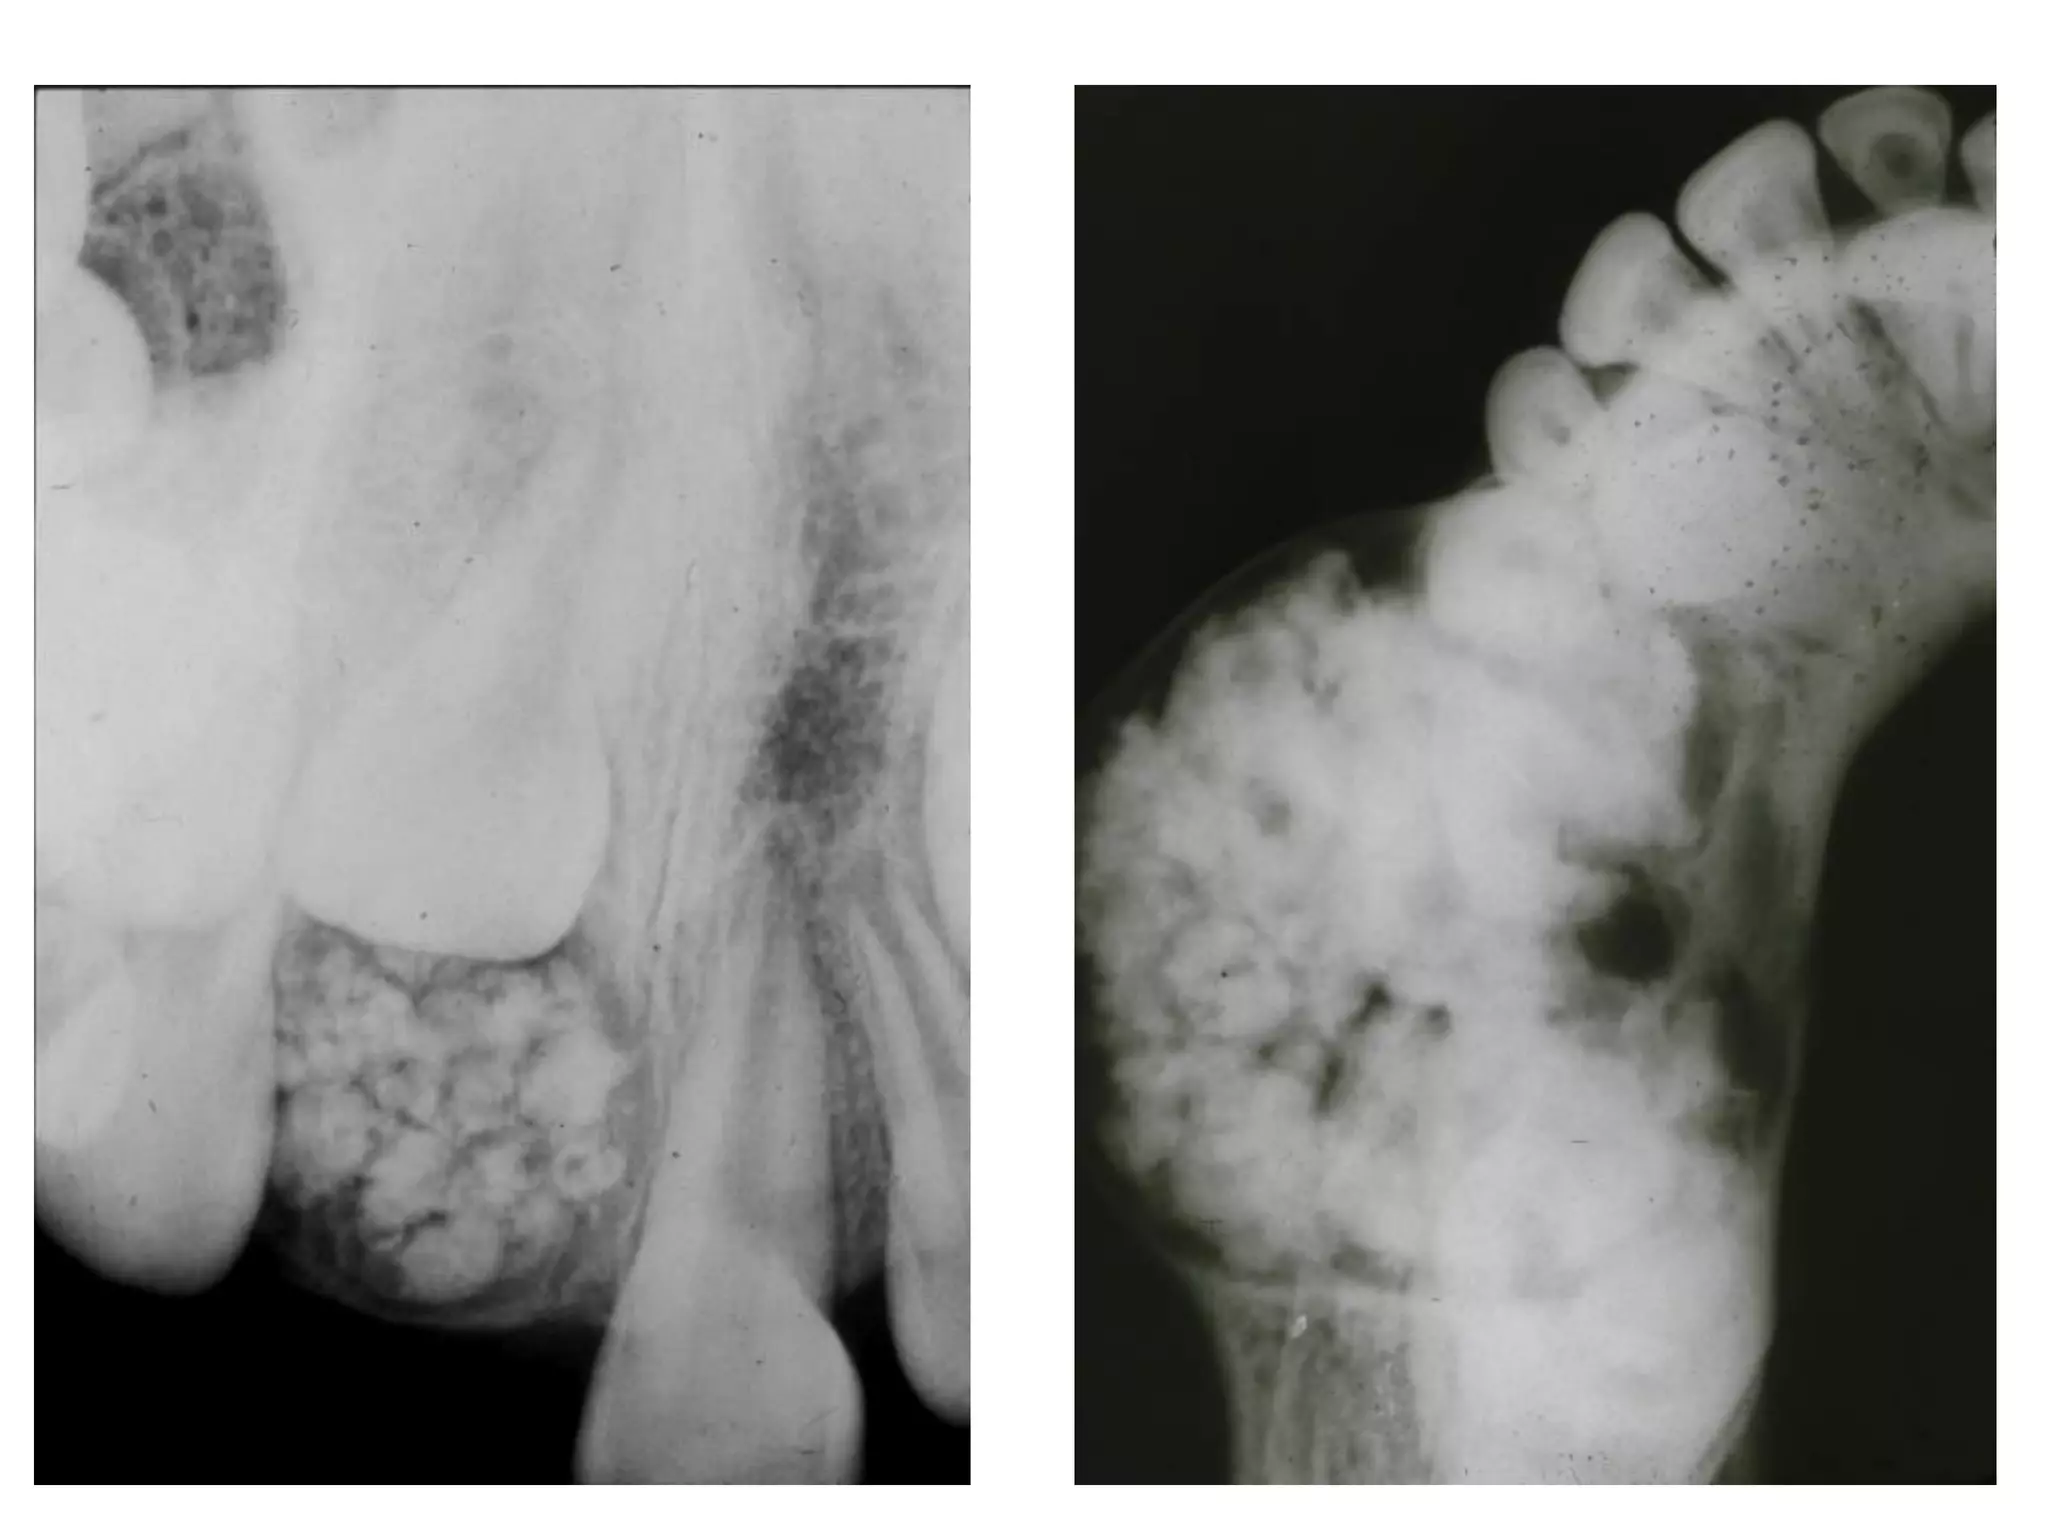

X quang:

 Sôùm: thaáu quang, ñöôøng vieàn roõ, nhaün.

 Muoän: caûn quang roõ.

 Daïng keát hôïp cho thaáy hình daïng raêng roõ

raøng trong khi daïng phöùc hôïp laø moät khoái caûn

quang ñoàng nhaát khoâng coù hình daïng raêng.

 U raêng keát hôïp (compound odontoma) goàm

men, ngaø vaø xeâ maêng saép xeáp thaønh hình

daïng raêng.

 U raêng phöùc hôïp (complex odontoma) goàm

men, ngaø vaø xeâ maêng nhöng saép xeáp ngaãu

nhieân, khoâng mang hình thaùi giaûi phaãu cuûa

moät raêng.